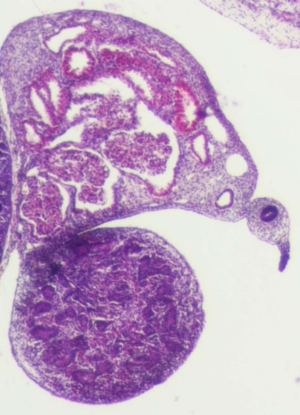

Stage 21

CfS 21

d37-39